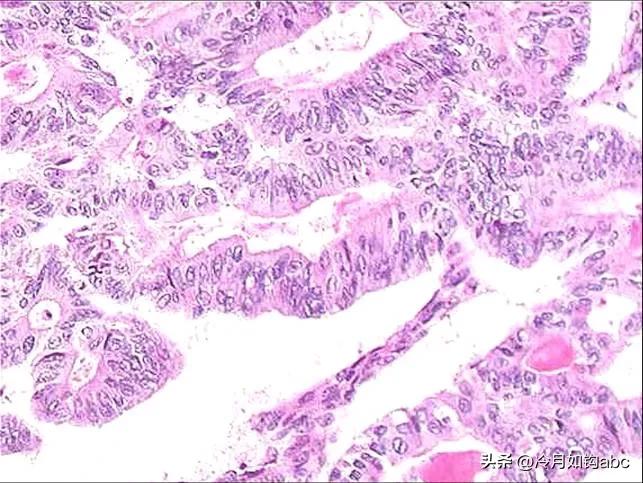

病理技师制作人体标本石蜡切片

病理医师在显微镜下阅读切片做诊断

人体标本石蜡切片显微镜下图像